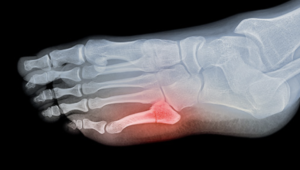

Ankle fractures occur when the bones in the ankle joint sustain a break as a consequence of an injury. Pain, swelling, bruising, tenderness and difficulty to bear weight are all common after ankle fractures.

Treatment:

The severity of the fracture as seen on an X-ray will determine the type of treatment that can range from a few weeks of leg support in a boot or surgery to fix the broken bones.

Our research:

I was awarded a grant to attend an American Academy of Orthopaedic Surgeons (AAOS) course in Baltimore, USA to discuss the management of difficult fractures amongst experts “Daily Dilemmas in Trauma: Your topics, expert solutions”. Staying up to date and engaging in continued debate with peers is a key part of our profession in this day and age. Link to AAOS Courses